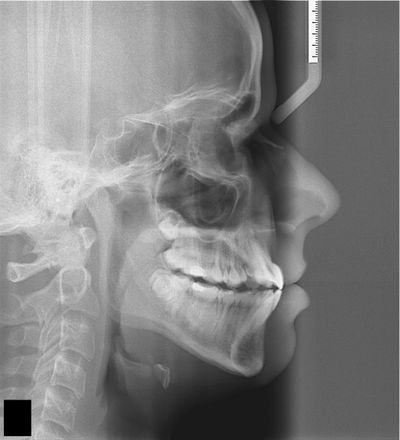

Easy Age freeware was developed by the Brazilian dentist Prof. Ms. Paulo E. Ferreira in 2010; it has the patent in the National Institute of Industrial Property (INPI); with the number BR 51 2014 000370 1; and it's used as an auxiliary tool for postgraduate students to improve their diagnostic capabilities for growing patients.

The first version was developed in Java; it is a Windows-only version and has been validated in my master's thesis in 2014.

In 2018 due to the Smartphones evolution, we developed an Easy Age version for Android 5.